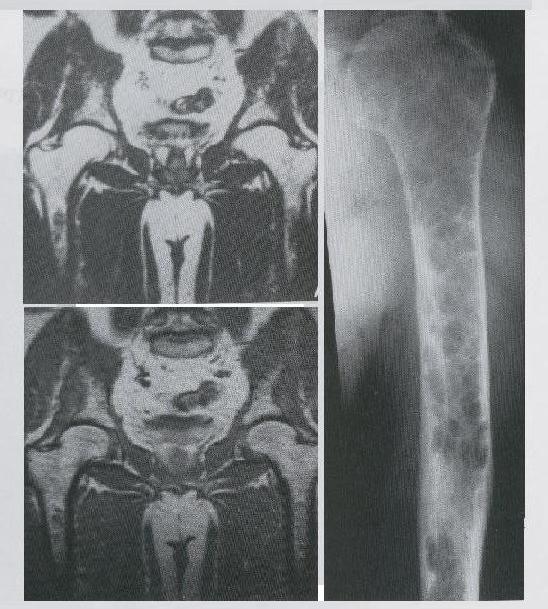

ESTUDIOS: RESONANCIA MAGNETICA DE PELVIS, RADIOGRAFIA SIMPLE DE HUMERO IZQUIERDO. EN LAS CUALES ENCONTRAMOS TUMORES